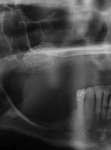

Figure 3D The site 6 months after surgery, confirming integration. Figure 4A Preoperative radiograph showing ridge resorption.

Figure 4B Radiographic confirmation of graft confinement and incremental addition.

Figure 4C Radiographic view of implant placed simultaneously with sinus bone grafting in site No. 3. Figure 4D Radiographic confirmation of the re-establishment of the sinus floor. Figure 4E Final implant-supported restoration.